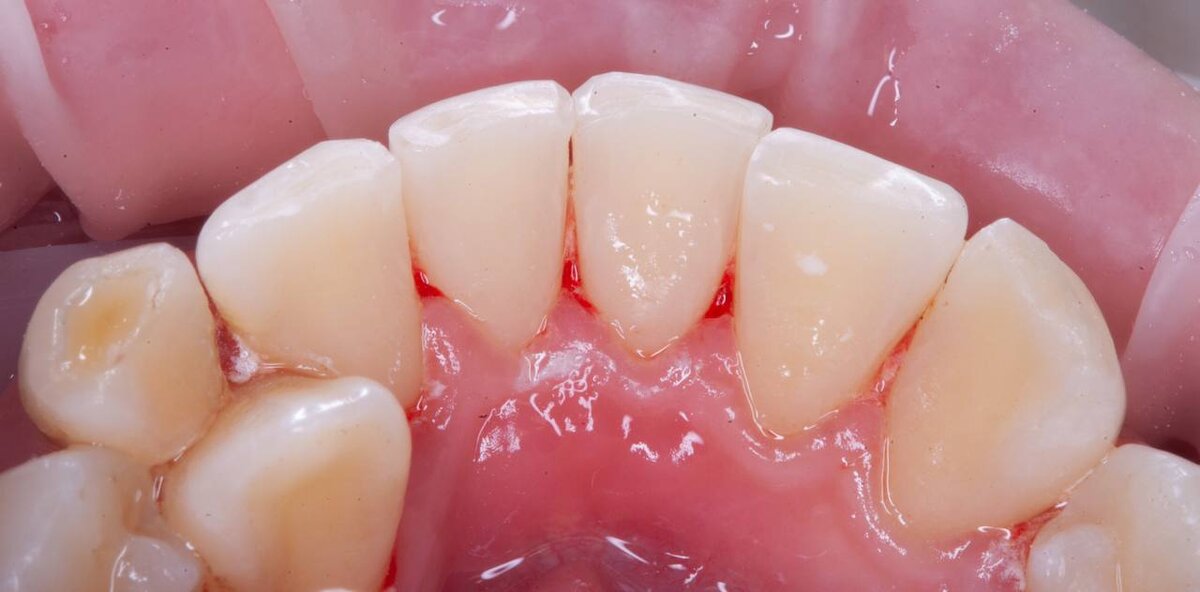

Эта фотопротокол - необходимый для стоматолога , чтобы наглядно показать пациенту отель проблемах в полости рта , а так же для проведения сравнения с результатом процедуры.

На данной фотографии, фото после проведения процедуры проф. гигиены. Фотографии из личного архива пациентов , не взятый из интернета. Наглядный пример «до» - «после».